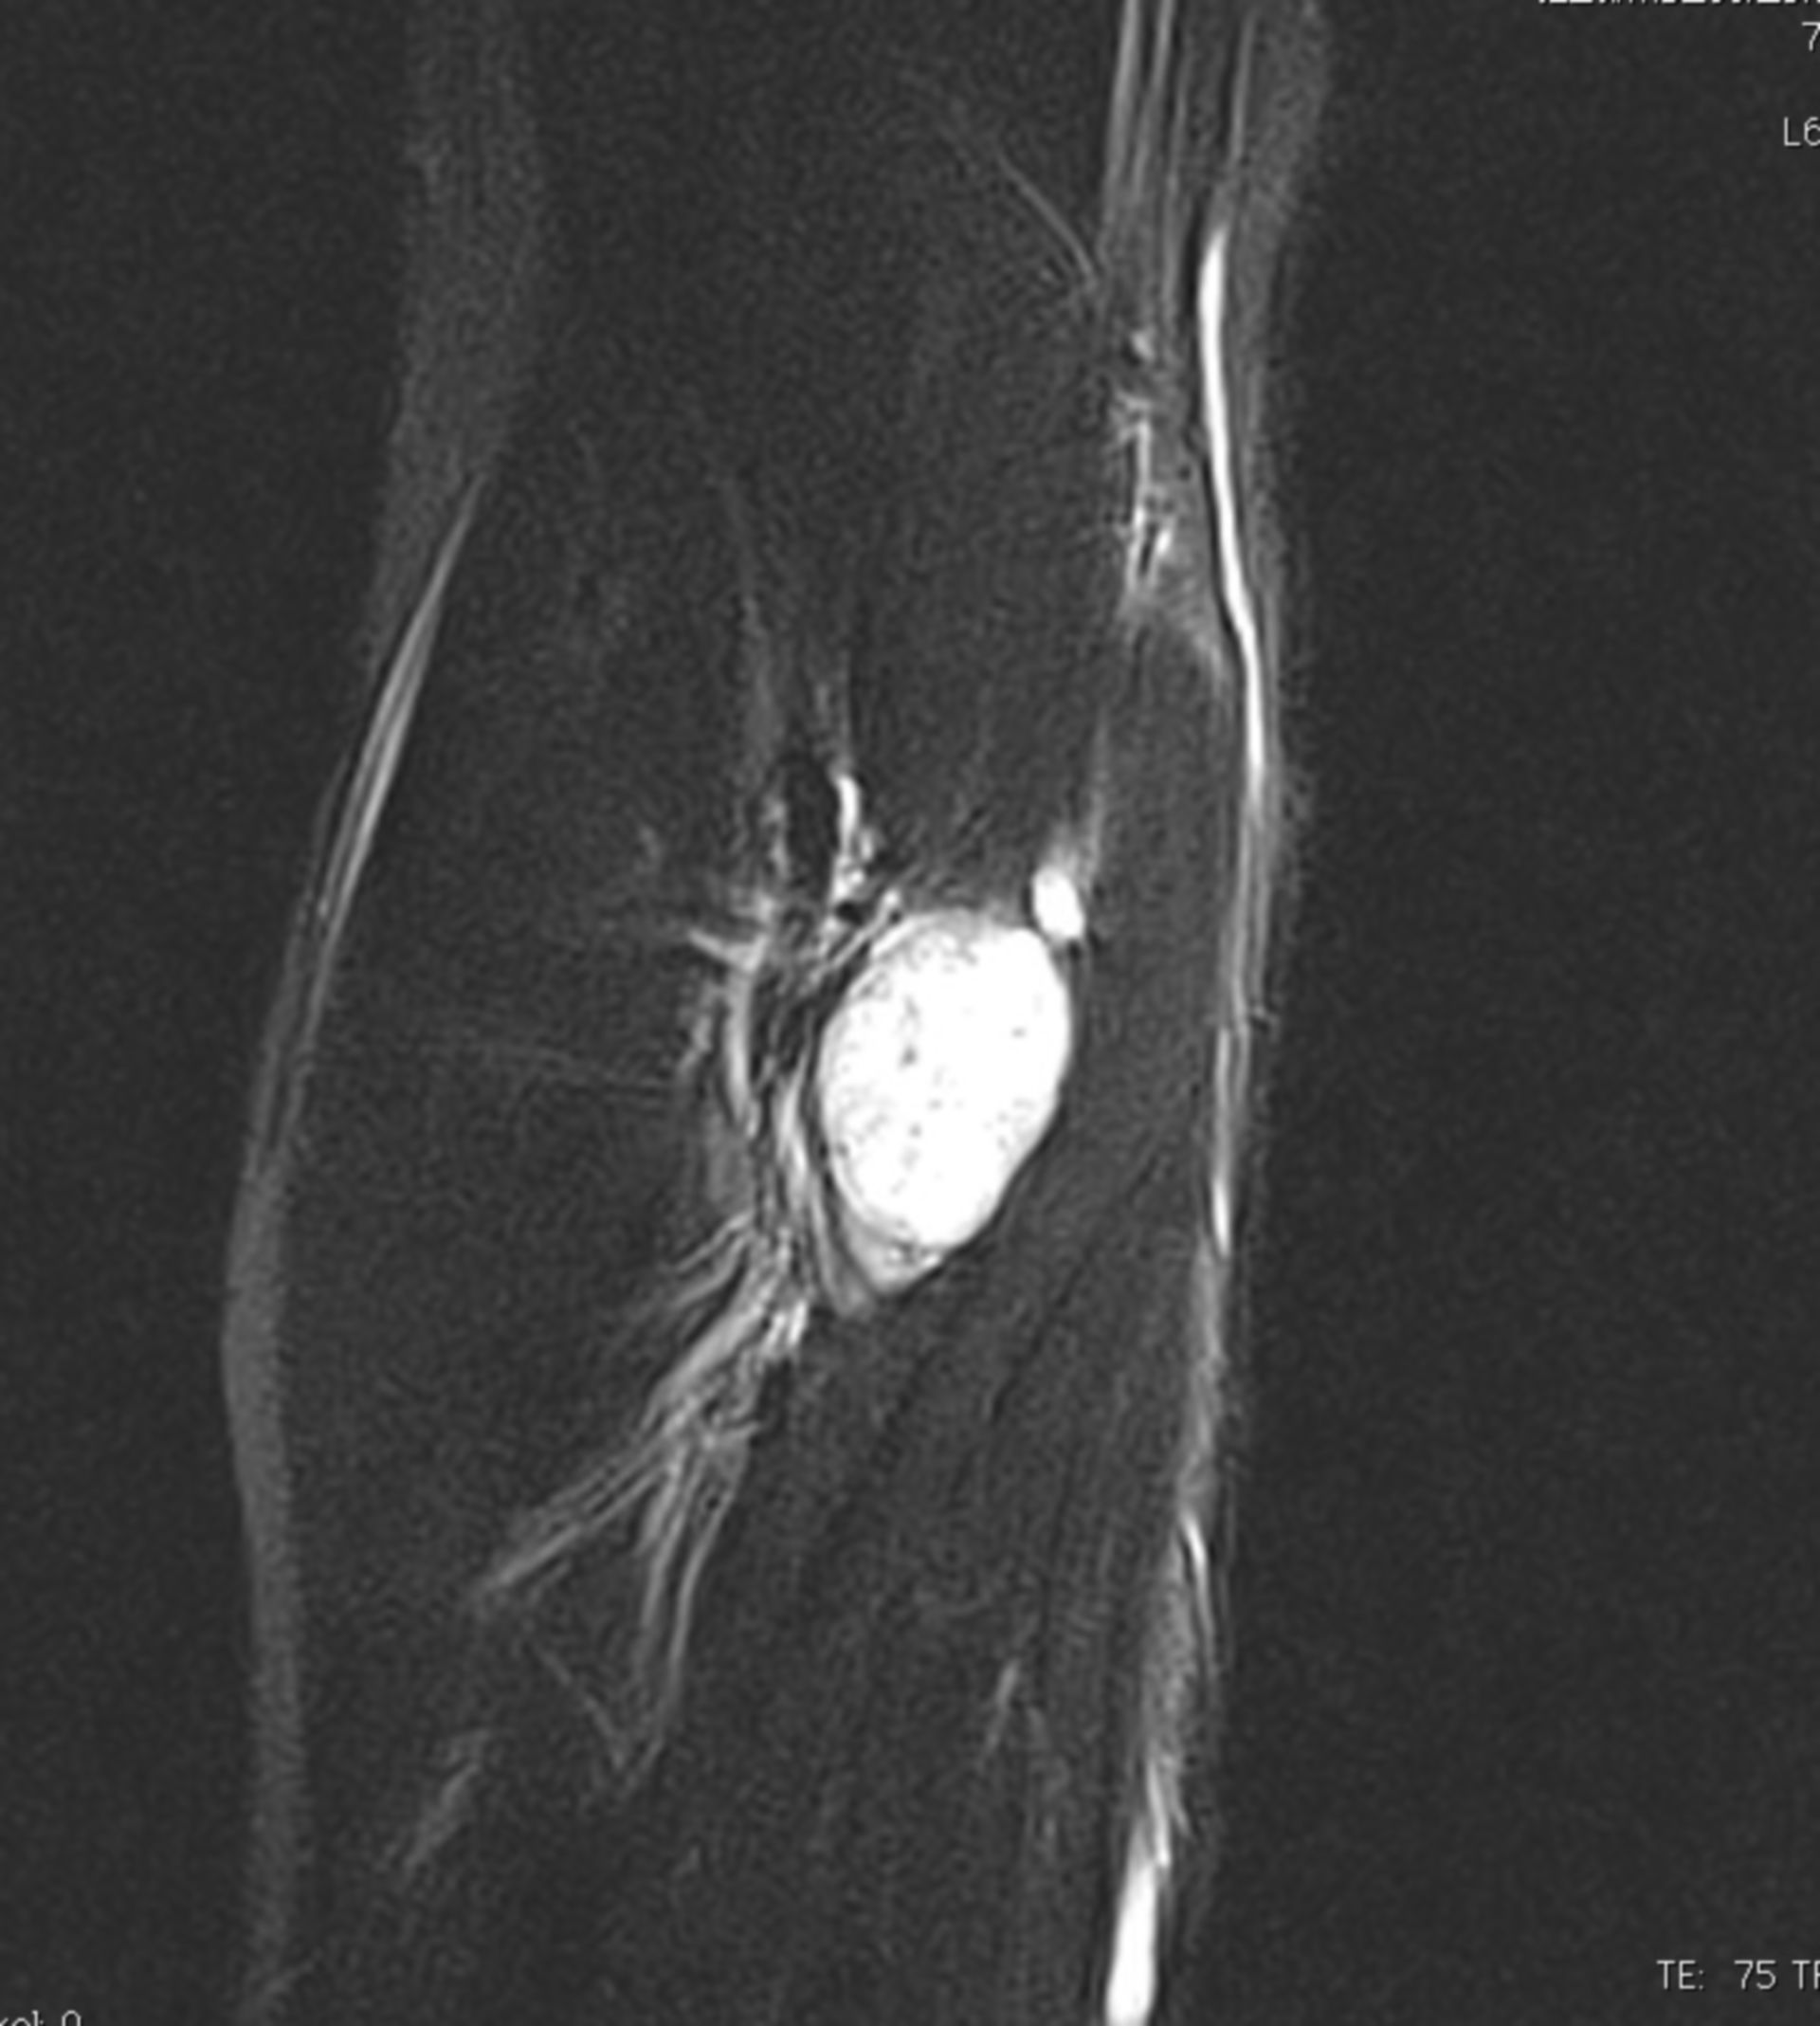

Mrt : Kuala Lumpur’s New MRT Map Alignment. ~ .: Property … / Support more model(qualcomm and … Retinoblastom (MRT/T2) – DocCheck

Neurinom N.medianus -MRT – DocCheck How to Get Around by Thailand MRT Subway – BestPrice Travel

MRT Knie – DocCheck MRT Niere3 – DocCheck

MRT Bild, könnte das ein Tumor sein? Kennt sich jemand damit aus? Könnte die helle Fläche ein … Myokarditis (MRT) – DocCheck

MRT: Knie – DocCheck MRT in der Krebsmedizin

?wer kann helfen?ist in diesen MRT ein Tumor sichtbar? MRT abdomen – DocCheck

MRT Knie links HWS ARTHROSE, MRT Stockfotografie – Alamy

Kreuzbandriss im MRT – Privatpraxis Dr. med. Severin Welter รีวิว 1441 Meal Box (MRT อิสรภาพ) – เนื้ออร่อยมา บรรจุปลอดภัย สะอาด – Wongnai

MRT Knie links MRT der akuten MS Stockfotografie – Alamy

Mrt Bilder – Meniskusriss? (Knie, Orthopädie, Chirurgie) (16/34) MRT Schädel in Sagittalebene, T₂‐gewichtet – DocCheck

MRT Knie links Mrt Bilder Schulter Sehnenriss – Captions Blog

MRT: Knie – DocCheck MRT Schädel – DocCheck

Knee Joint Mri Stockfotos und -bilder Kaufen – Alamy MRT Thorax – DocCheck

MRT: Knie – DocCheck MRT Knie links

MRT Knie linksสถานีMRTแทบแตก? คนเยอะมาก รถไฟไทย🇹🇭พามาดูความลึกความยาวสถานีสามยอดไทยสร้างได้ไง!ความลึกเท่าตึก3ชั้น😯